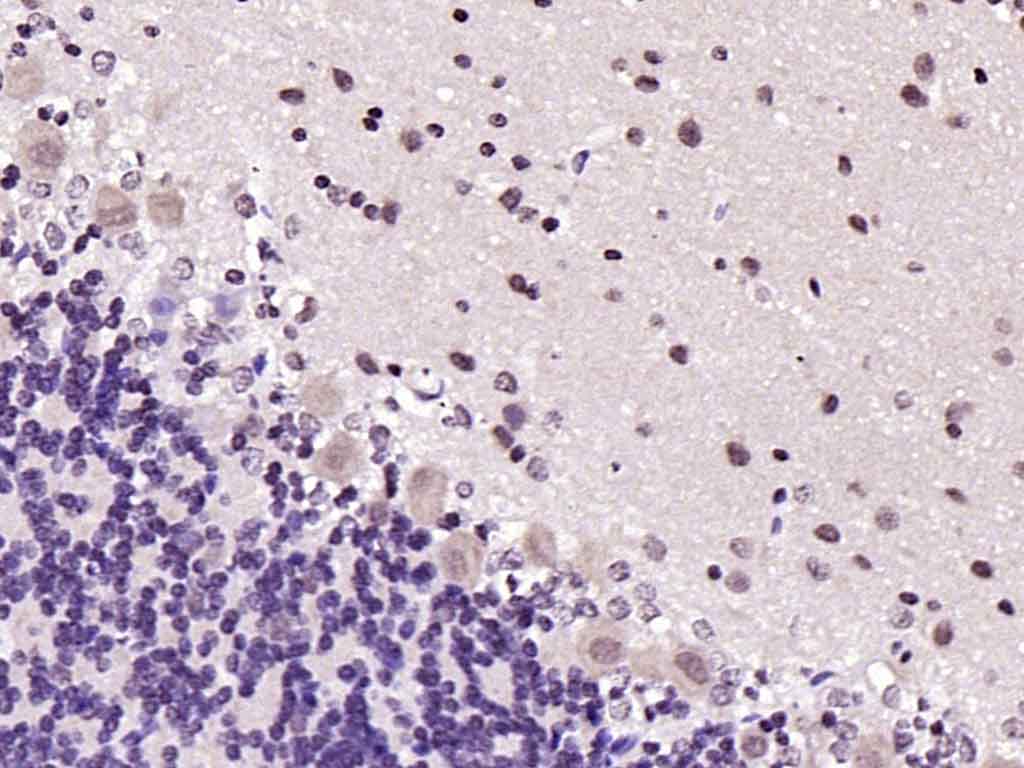

| 产品应用 | IHC-P=1:100-500, IHC-F=1:100-500, ICC/IF=1:100-500, IF=1:100-500, Flow-Cyt=2ug/Test Not yet tested in other applications. |

| {IHC-P} | {1:100-500} |

| {IHC-F} | {1:100-500} |

| {ICC/IF} | {1:100-500} |

| {IF} | {1:100-500} |